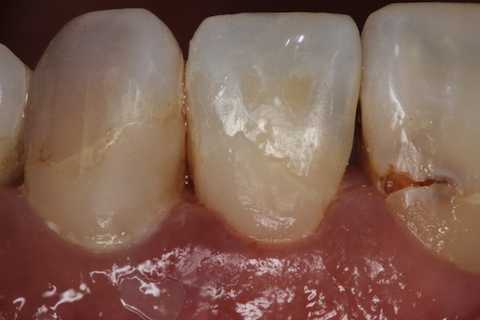

とりあえず健全歯質を確保して、露髄部分は直覆してCRで再建した。

では時系列で、どうぞ